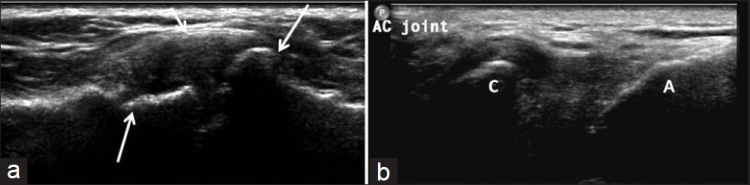

La ecografía del hombro comienza examinando el surco bicipital (BG) y la cabeza larga del tendón del bíceps braquial. El paciente está sentado frente al operador en una posición neutra, su mano colocada con la palma hacia arriba sobre el muslo. Se realiza una imagen de eje corto colocando el transductor sobre la metáfisis humeral proximal perpendicular al húmero. La imagen del eje largo del tendón se obtiene girando el transductor a una posición paralela a la diáfisis humeral [Figura 1]. Luego, se examina el tendón del subescapular. El brazo del paciente se fija sobre el flanco y el antebrazo se abduce en rotación externa. Se realizan vistas de eje largo y corto del tendón [Figura 2]. Los tendones infraespinoso y redondo menor se examinan desde una vista posterior del hombro. El paciente se gira 90°, su mano se coloca sobre el hombro opuesto y el transductor se orienta en el plano axial sobre la cabeza del húmero [Figura 3]. La articulación glenohumeral y la escotadura espinoglenoidea también se examinan en una vista posterior del hombro. El transductor ahora se mueve medial y caudalmente en el plano transversal hasta que se vea el margen posterior de la articulación glenohumeral y luego, más medialmente para mostrar la escotadura espinoglenoidea [Figura 4]. El tendón supraespinoso se escanea en una vista anterior del hombro. El paciente está sentado frente al operador. El brazo del paciente se coloca en una posición posterior, la mano dorsal en el ala ilíaca opuesta o la mano palmar en el ala ilíaca ipsilateral. Se obtienen vistas de eje largo y corto del tendón supraespinoso. Luego se realiza la exploración del manguito de los rotadores durante las maniobras dinámicas. El transductor se coloca sobre el acromion. El brazo del paciente se abduce con el codo flexionado a 90° o/y el brazo se extiende anteriormente [Figura 5]. Finalmente, se escanea la articulación acromioclavicular. La mano del paciente se coloca con la palma hacia arriba sobre el muslo. El transductor se coloca sobre la parte superior del hombro en un plano coronal [Figura 6].

Derrame de la articulación gleno-humeral [Figura 17], derrame de la bursa subacromial-subdeltoidea [Figura 18], bursitis calcificante [Figura 19], artropatías y dislocaciones de la articulación acromioclavicular [Figura 20], rotura del tendón del bíceps [Figura 21], sinovitis [Figura 22] y la luxación [Figura 23] son las principales patologías no relacionadas con el manguito rotador que se observan en la ecografía de hombro [Tabla 3]. [8-9] La ecografía es sensible para la detección de derrame de la articulación glenohumeral y derrame bursal subdeltoideo subacromial, incluso en pequeñas cantidades. La aspiración de líquido bajo guía ecográfica permite un diagnóstico preciso. La penetración intrabursal de depósitos calcificados en el tendón provoca una bursitis microcristalina aguda y dolorosa. La subluxación o dislocación de la articulación acromioclavicular aparece como un ensanchamiento de la cavidad articular y un abultamiento de la cápsula superior y el ligamento. La rotura de la cabeza larga del tendón del bíceps braquial suele generar un bulto en la parte anterior del brazo, conocido como "signo de Popeye". La rotura del tendón suele ocurrir a nivel intrarticular con retracción distal, dejando un surco vacío. En los desgarros agudos, el muñón del tendón aparece rodeado de líquido. La luxación del tendón del bíceps medial se diagnostica con ecografías transversales, que muestran el surco bicipital y el tendón que recubre la tuberosidad menor.#dieciséis#